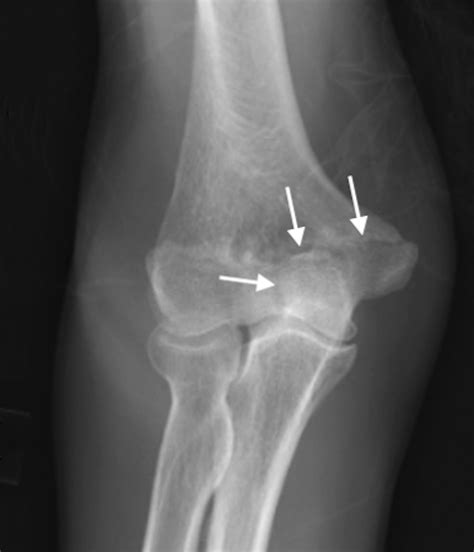

Diagnosing issues related to the trochlea of humerus typically involves a combination of physical examination, imaging tests, and medical history. A healthcare provider may use X-rays, MRI, or CT scans to visualize the trochlea of humerus and surrounding structures. These tests can help to identify fractures, arthritis, or other conditions that may be affecting the elbow joint.